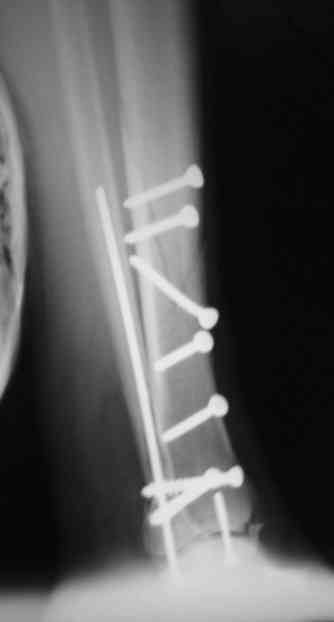

Re: Сложный внутрисуставной перелом голени

Антон Лебединец 29 Апрель 2007, 22:01

Рентгенограммы